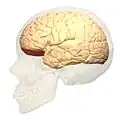

Поле Бродмана 11 в мозге человека

Поле Бродмана 11, или BA11, является частью лобной коры в мозге человека, орбитофронтальной коры, которая покрывает медиальную часть вентральной поверхности лобной доли.

Префронтальное Поле Бродмана 11-1909 является структурным подразделением лобной доли человека, что определено на основе цитоархитектоники.

Поле 11 представляет большинство орбитальных извилин, прямую извилину и наиболее ростральную часть верхней лобной извилины. Она граничит медиально с нижней ростральной бороздой и латерально с фронтомаргинальной бороздой. Цитоархитектонично граничит рострально и латерально с полем 10, полем 47, и полем 45; на медиальной поверхности граничит дорсально с полем 12 и каудально с полем 25. Известно, что префронтальное поле 11 образца 1909 года было больше; оно включало нынешнюю часть поля 12.[4]

Изображения

вид спереди. Боковой вид.

Боковой вид.